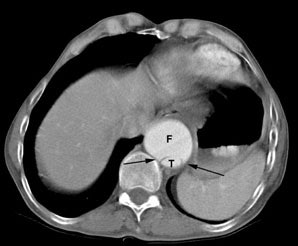

The "beak sign" is demonstrated by the image on the left. In this acute dissection small beaks of contrast (black arrows) extend from the false lumen (F) around the margins of the true lumen (T). The false lumen (F) is also commonly larger than the true lumen (T). |